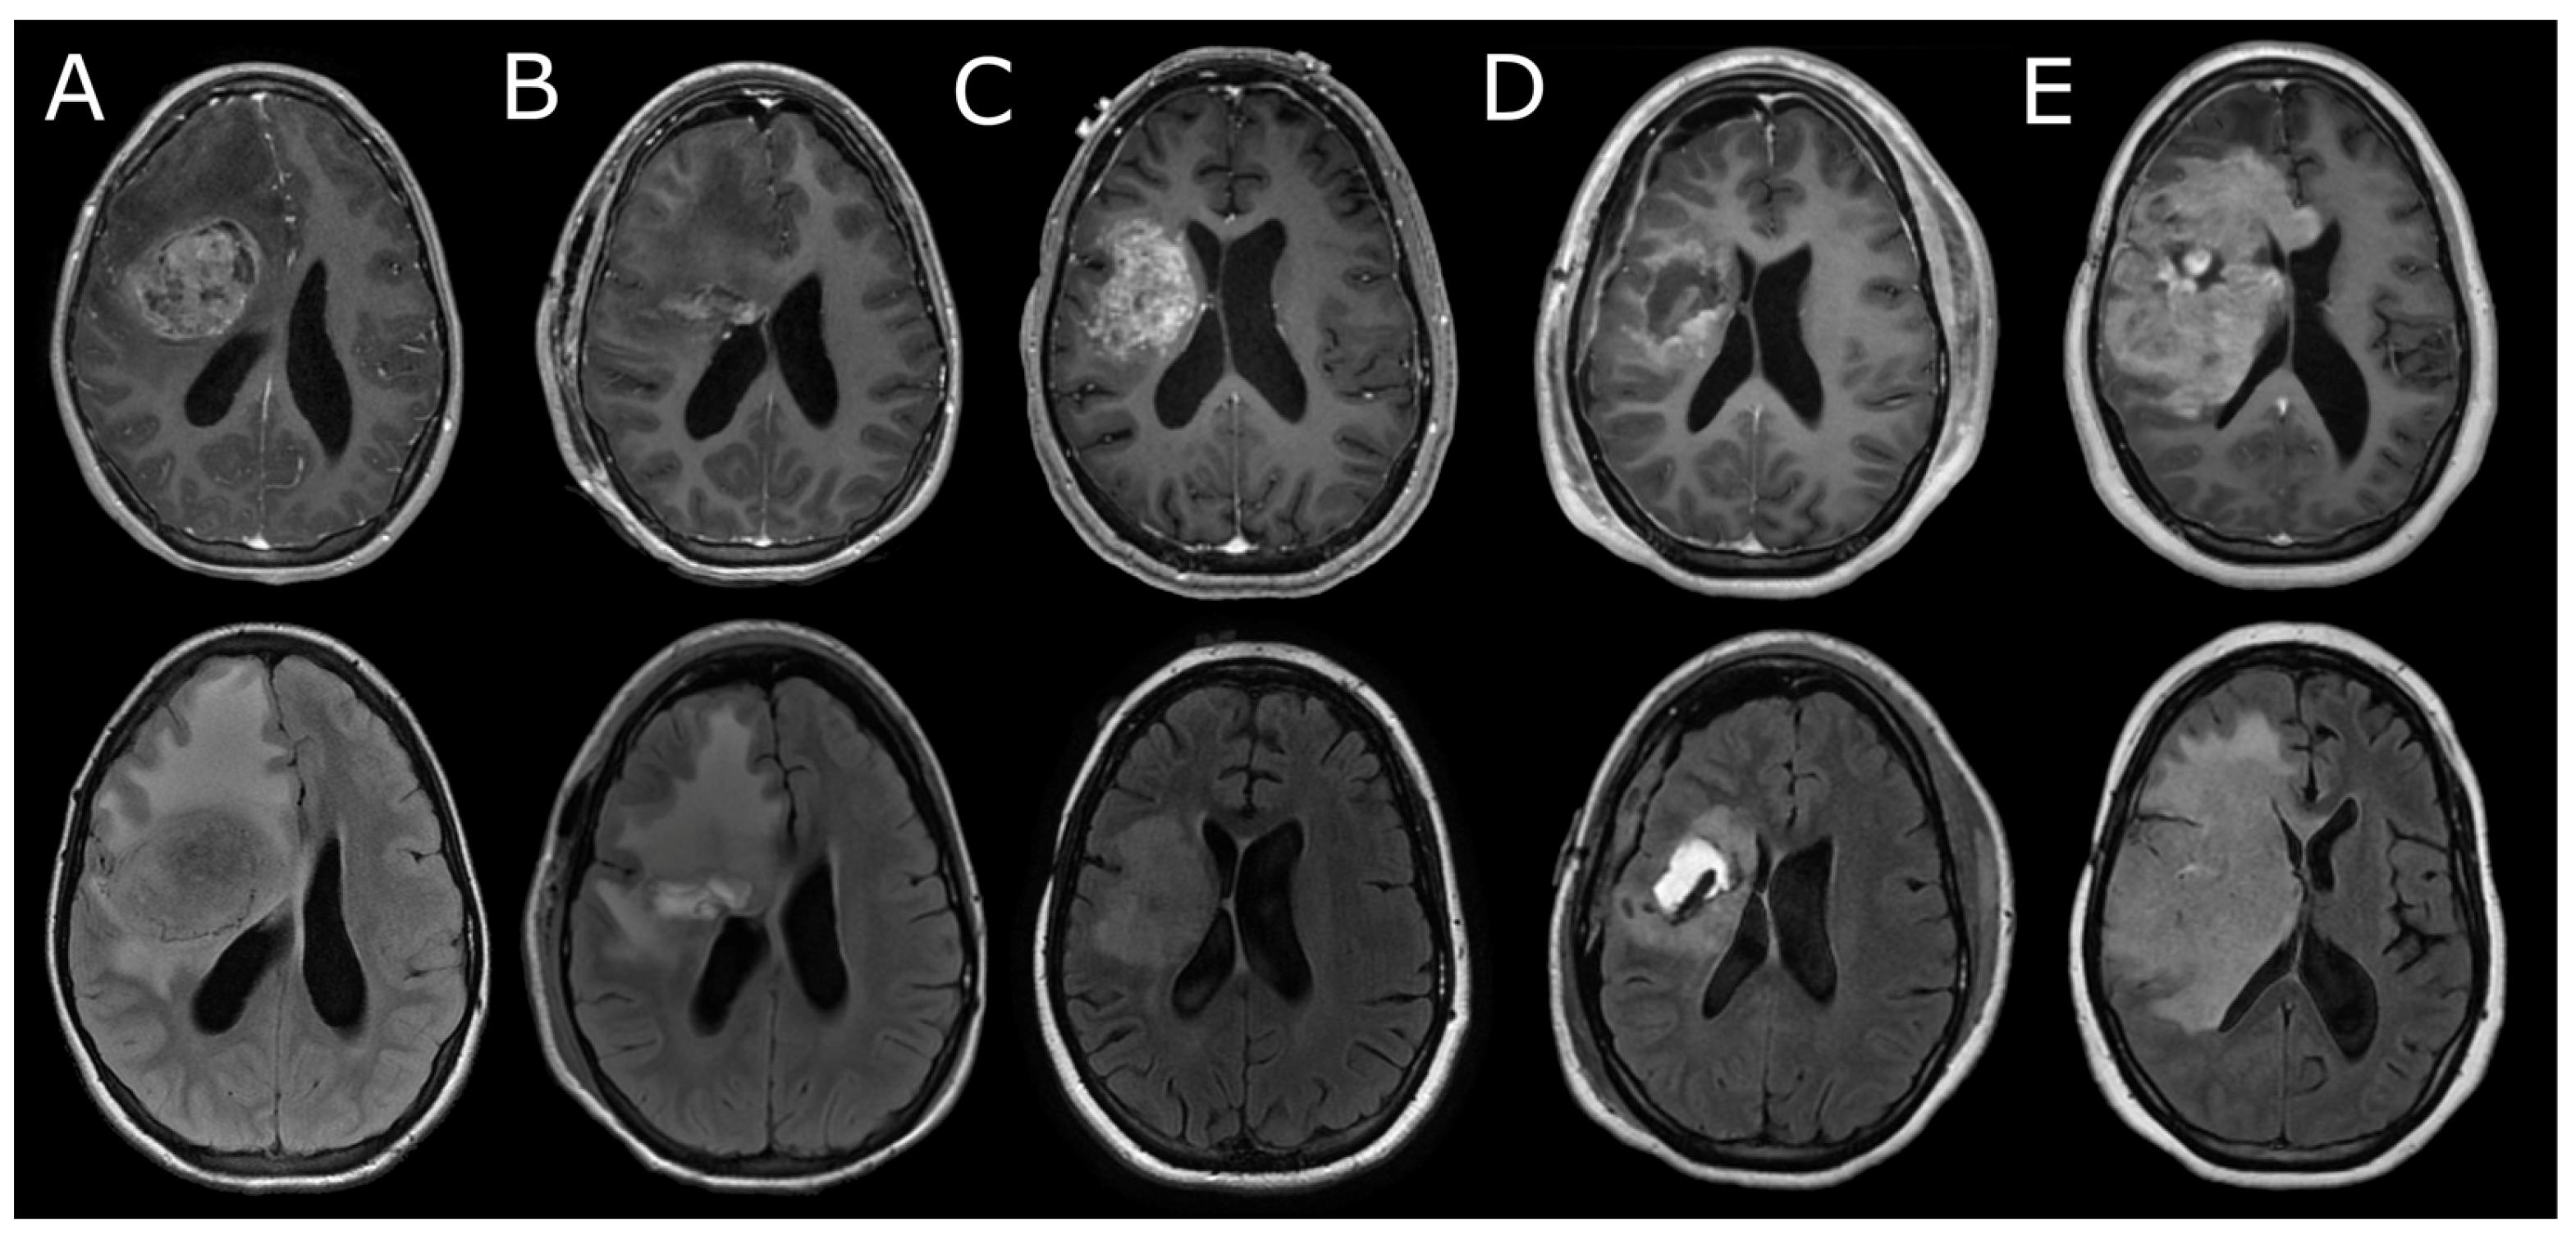

3.3. Neuroimaging